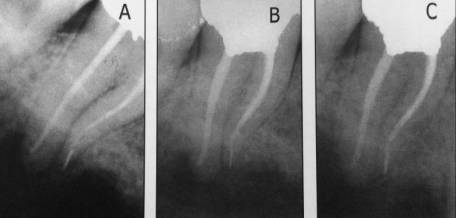

Снимок определения рабочей длины. Виден ByPass сломанного

инструмента.

Снимок наблюдения через 6

месяцев. Практически полное исчезновение периапикальных процессов на М и Д

корнях